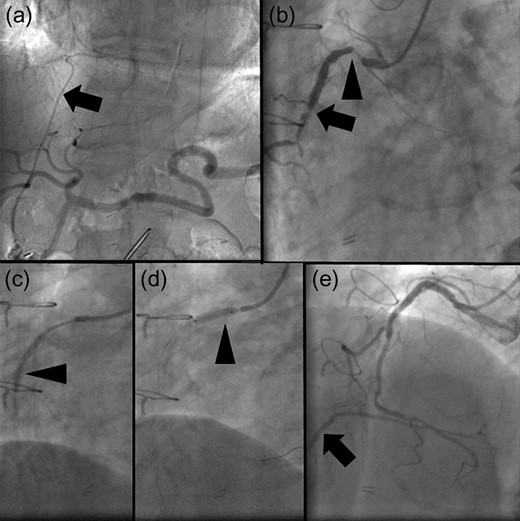

The patient underwent coronary arteriography preoperatively. Based on confirmation of a patent RGEA (Fig. 1a), the stenotic native coronary artery was revascularized (Fig. 1b) using bare-metal stents (BMS) to avoid cardiac ischemia due to intraoperative manipulation of the RGEA (Fig. 1c–e). Definitive gastric surgery was performed 4 weeks after revascularization. The location of the RGEA was easily confirmed intraoperatively (Fig. 2a). Indigo carmine dye was administered into the greater curvature of the gastric angle, adjacent to the tumor, to observe the lymph stream, through which the infrapyloric lymph ducts could also be observed (Fig. 2b). We detached the adipose tissue bearing lymphatic tissue along the outermost layer of nerves that twine around the surface of the pancreas and anterior superior pancreaticoduodenal vein [7] (Fig. 2c). After the lymphatic tissue was removed along the outermost layer of nerves, the remaining skeletonized RGEA was preserved (Fig. 2d). Histopathologically, the tumor was 35 × 25 mm2, type 3, por2, pT3, pN0. Heparin treatment was initiated on postoperative day (POD) 1. However, it was interrupted from PODs 6 to 13 because of a transient hematic discharge from the drainage tube, and antiplatelet therapy was reinitiated on POD 15. The patient was discharged on POD 18. Over the 41-month follow-up period, he did not experience any recurrence of the gastric cancer or cardiac ischemia.

(a) The right gastroepiploic artery (RGEA) at the start of the surgery (arrowhead). (b) Lymph flow from the gastric angle is observed in the infrapyloric lymph ducts using indigo carmine dye (arrowheads). (c) The translucent, whitish autonomic nerves that twine around the surface of the pancreas and the anterior superior pancreaticoduodenal vein can be observed during dissection along the outermost layer of nerves. (d) The RGEA is preserved after infrapyloric lymphadenectomy (arrow).

According to the Japanese Gastric Cancer Association guidelines, dissection of infrapyloric LNs, which encompass the first branch and proximal part of the RGEA, is required for distal and total D1 and D2 gastrectomies for gastric cancer [1, 2]. Although CABG using the RGEA may lead to certain changes in the lymph stream, metastasis to the infrapyloric LNs is common among patients with gastric cancer even after CABG using the RGEA [3, 4]. In our case, there were no swollen LNs. However, we confirmed that the lymph stream from the gastric antrum toward the infrapyloric area was maintained (Fig. 2b), which suggested the need for preventive infrapyloric lymphadenectomy.